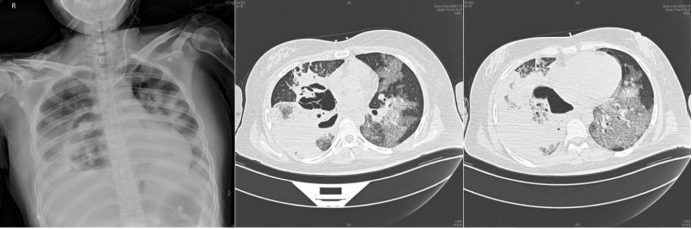

病例1:女性,22岁,既往有1型糖尿病病史,在感染新冠病毒后合并毛霉(米根霉)感染。影像学检查显示双肺存在磨玻璃影,且在此基础上迅速出现实变、空洞及坏死等病变,病情进展极为迅猛(图1)。该患者于2022年底(新冠疫情优化管控后疫情较为严峻时期)从内蒙古前往北京就医,进入急诊室当天便因呼吸衰竭不幸死亡。此病例凸显COVID-19合并毛霉感染的严重性,尤其是对于存在基础疾病(如糖尿病)的患者,病情可快速恶化,致死性极高,也反映出在疫情特殊时期,此类重症感染患者救治面临的严峻挑战。

图片

1  病例1影像学表现